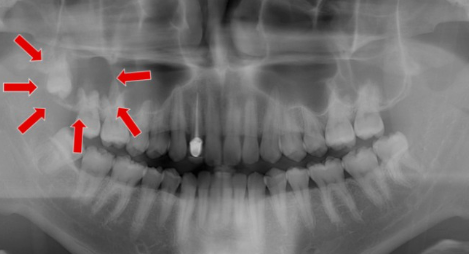

사랑니 발치는 일반 치아와 달리 신경과 가까이 있어 신경 손상 가능성이 있습니다. 하지만, 사랑니 발치를 해야 하는 경우 위험 부담이 있더라도 사랑니를 빼게 됩니다. 제3대구치라고도 불리는 사랑니는 어금니 맨 끝 쪽에 위치하고 있고 맹출 시기는 보통 17~21세 사이로 알려져 있습니다.

구강 내 모든 치열이 완성되고 뒤늦게 자라나는 사랑니는 제대로 맹출 되는 사람도 있지만, 옆으로 누워서 나거나 매복 상태로 통증만 지속되는 경우가 많습니다. 사랑니의 맹출 상태, 관리 방법에 따라 영구치로 유지하는 경우와 발치해야 하는 경우로 나뉩니다.

2022년 사랑니 발치 비용 사랑니 발치는 위치, 맹출 상태, 치아 뿌리 상태에 따라 5가지 형태로 분류되며 사랑니 발치 비용이 달라집니다.

사랑니 발치 비용은 난이도에 따라 비용이 달라지며 매복이 심한 경우 발치가 불가능하기도 합니다. 난도가 높은 사랑니 발치 시 CT 장비를 갖춘 병원급 or 대학병원에서 발치하길 권장합니다. 사랑니 발치는 무조건 해야 하는 것은 아니며, 제대로 맹출 되었다면 제3대구치로 사용이 가능합니다.